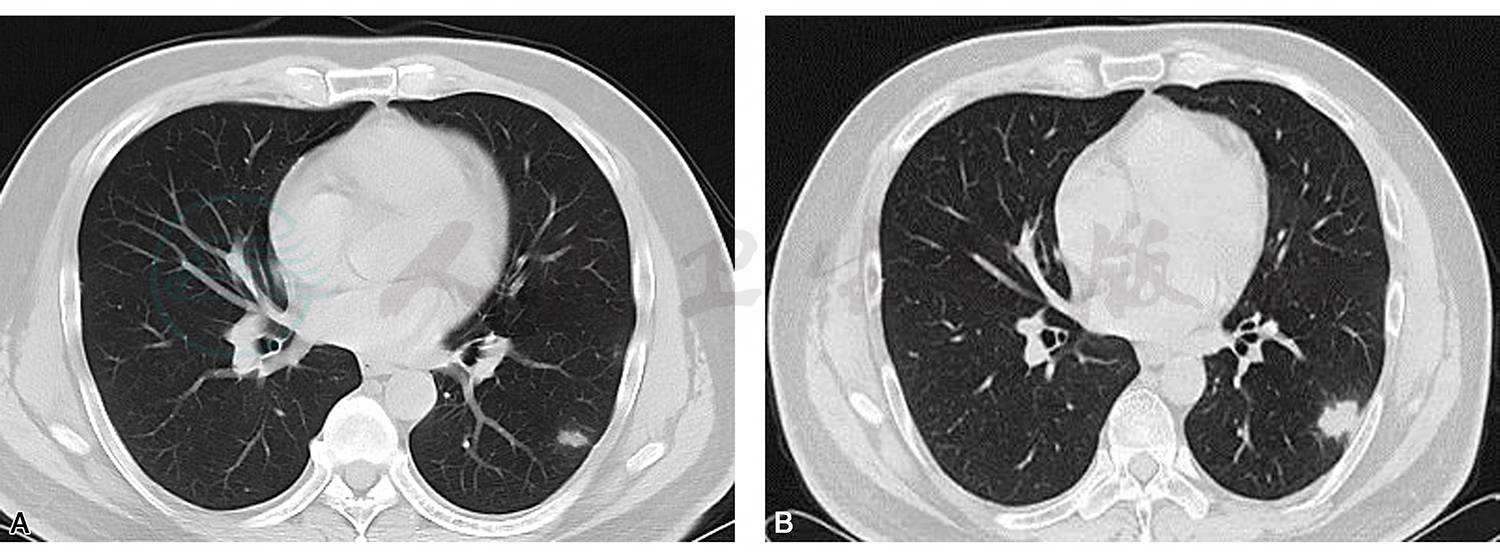

患者男性,42岁,某五星级酒店厨师。主因“咳嗽伴发热1个月”就诊。患者于2018年2月13日无明显诱因出现咳嗽,干咳为主,伴发热,体温最高38℃,无胸闷、胸痛,无咯血气、促等不适。于我院急诊查血白细胞:2.9×109/L,中性粒细胞比例:22%,CRP:正常;行胸部CT扫描(2018-02-14)示:左肺下叶多发斑片、结节影(图1A)。予“左氧氟沙星联合头孢曲松”静滴抗感染治疗,1天后体温渐恢复正常,改为“头孢克洛”口服抗感染治疗,期间咳嗽无明显缓解。门诊复查血常规示白细胞在正常范围,胸部CT扫描(2018-03-14)示:“左肺下叶多发斑片影,病灶较前进展”(图1B)。现为进一步诊治收住我科。患病以来精神好,胃纳可,睡眠好,大小便正常,体重无明显下降。

图1 胸部CT平扫:左肺下叶基底段多发斑片、结节影伴晕征(A);门诊抗生素治疗1个月后复查胸部CT示左肺下叶病灶较前明显进展(B)

胸部CT扫描(见图1)。

综合分析患者病情有如下特点:①中年男性,急性起病;以咳嗽伴发热1个月就诊;②化验血象、CRP均正常;③胸部CT示左肺下叶斑片、结节影伴晕征;④抗生素治疗后复查胸部CT提示左肺下叶病灶较前有进展。综合上述特点,考虑感染可能性大。为明确病原学诊断,实现目标治疗,我们完善了以下检查:

患者病情特点总结:①以咳嗽伴发热急性起病;②胸部CT示左下肺多发实性结节影伴晕征,1个月内复查病灶有进展;③乳胶凝集试验阴性,但是肺泡灌洗液中查见新型隐球菌,依据病原学为确诊金标准的原则,患者最终诊断肺新型隐球菌病。进一步追问病史,患者系五星级酒店厨师,经常接触家禽和鸟类等,有可疑家禽、鸟类粪便接触史。新型隐球菌(pulmonary cryptococcosis)是一种在世界范围内广泛分布的有荚膜包绕的酵母菌。感染初期,多数病人可无症状。少数病人出现低热、轻咳,咳黏液痰。X线表现为多形性,轻者仅表现为双肺下部纹理增加或孤立的结节状阴影,偶有空洞形成。此例患者临床与影像学表现符合肺隐球菌病。